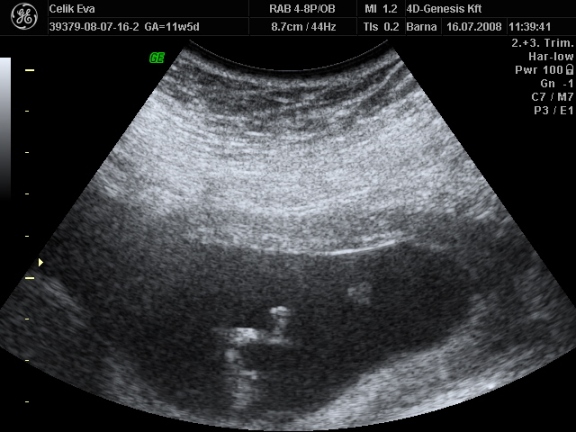

2d-s

ezen olyan aranyos baba arca van :lol: Kép

Kép Kép Kép

asiye

és a fütyi:

mindegyik deréktól lefelé van, a hasikájának a fele látszik, a lábacskákés közte a fütyi

az első kettő majdnem egyforma

a harmadik is deréktól lefelé de oldal irányból, itt talán jobban látszik a feneke alatt a fütyi mérete :lol:

érdemes a tappancsokat is megnézni :lol: